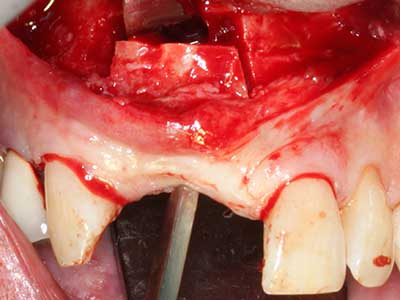

Piezosurgery has additional advantages when harvesting bone blocks. In addition to the high precision with osteotomy described above, the use of the thin saw tips specifically minimizes loss of material. Greater loss of material during harvesting can be expected with the thicker instrument tips, particularly when using Lindemann drills (Lakshmiganthan, Gokulanathan et al. 2012). The basal separation, which is necessary particularly for retromolar block transplants, is simplified by specially designed rectangular saws, with the result that piezosurgery is viewed as a precise, simple and safe procedure for harvesting retromolar bone blocks (Happe 2007) (Fig. 1-12).